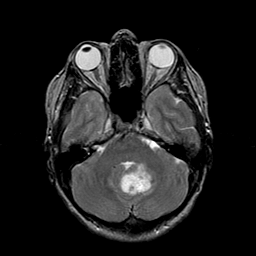

Metastatic Adenocarcinoma of the Colon: T2-weighted MR -- Slice #7

[Home][Help][Clinical] Slice 7